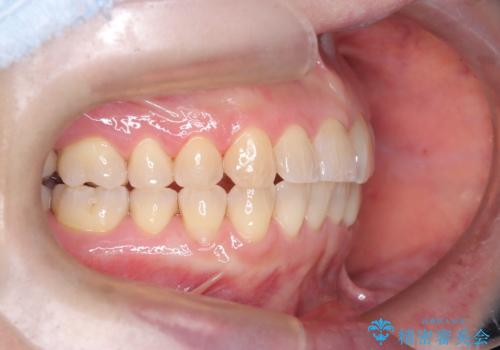

今回の矯正治療では、歯の色に近い目立たない審美ブラケットとワイヤーを使用しました。

スペース確保のために、まず奥歯全体をわずかに後方へ動かす遠心移動を実施し、前歯を並べるためのスペースを確保。さらに、安全性に配慮しながら歯の側面をわずかに削るIPRを併用し、デコボコを解消しました。

ワイヤー矯正ならではの確実な歯のコントロールにより、当初の計画通り約1年という短い期間で、前歯のガタつきが解消。見た目が美しく整っただけでなく、清掃しやすい機能的な歯並びを獲得していただけました。